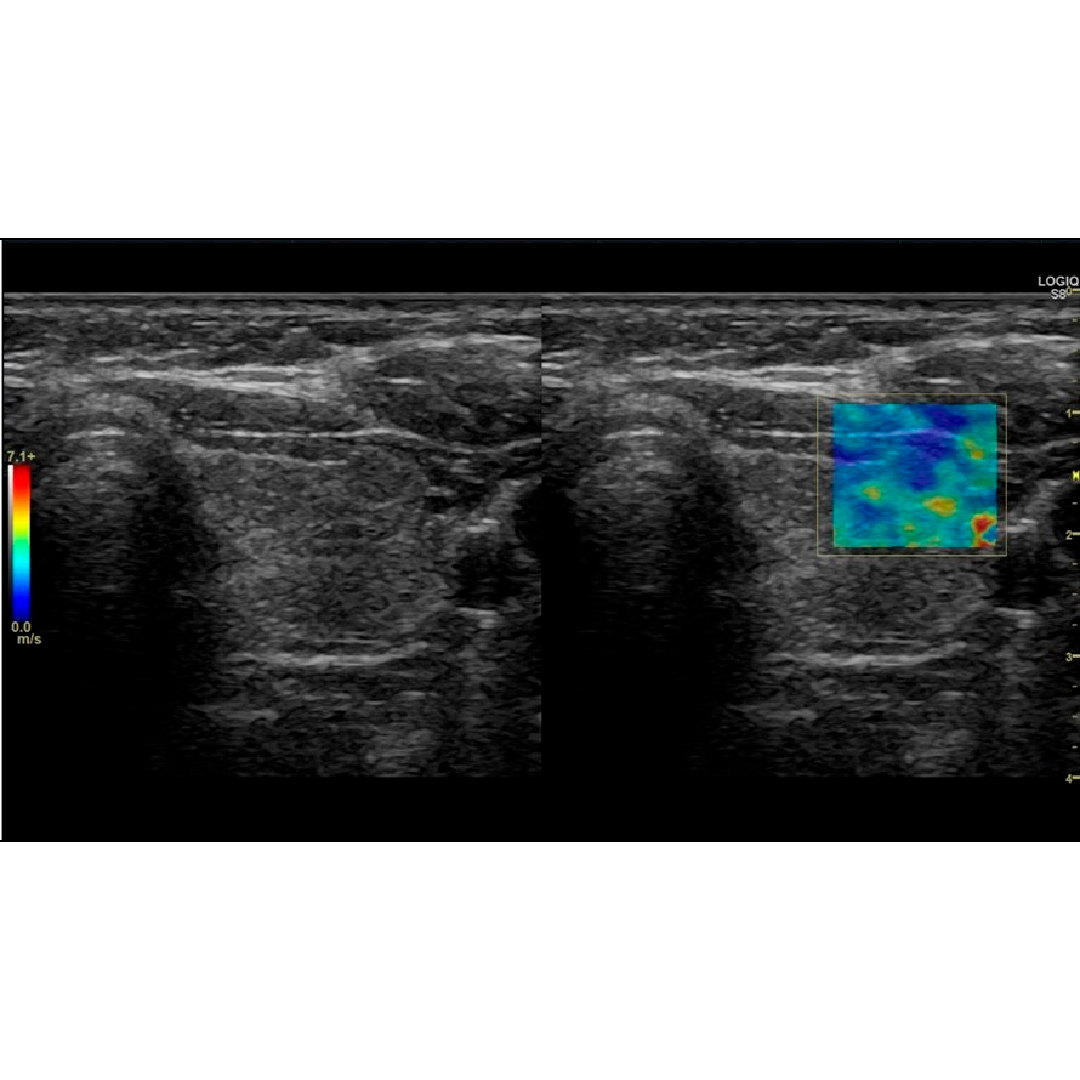

Elastografía por ondas de corte en 2D

Proporciona una evaluación cuantitativa y no invasiva de la rigidez tisular y se puede utilizar con la navegación volumétrica.

Imágenes clínicas

El equilibrio entre rendimiento y precio en un examen ligero y portátil. Vea y cuantifique la enfermedad hepática en un solo examen.